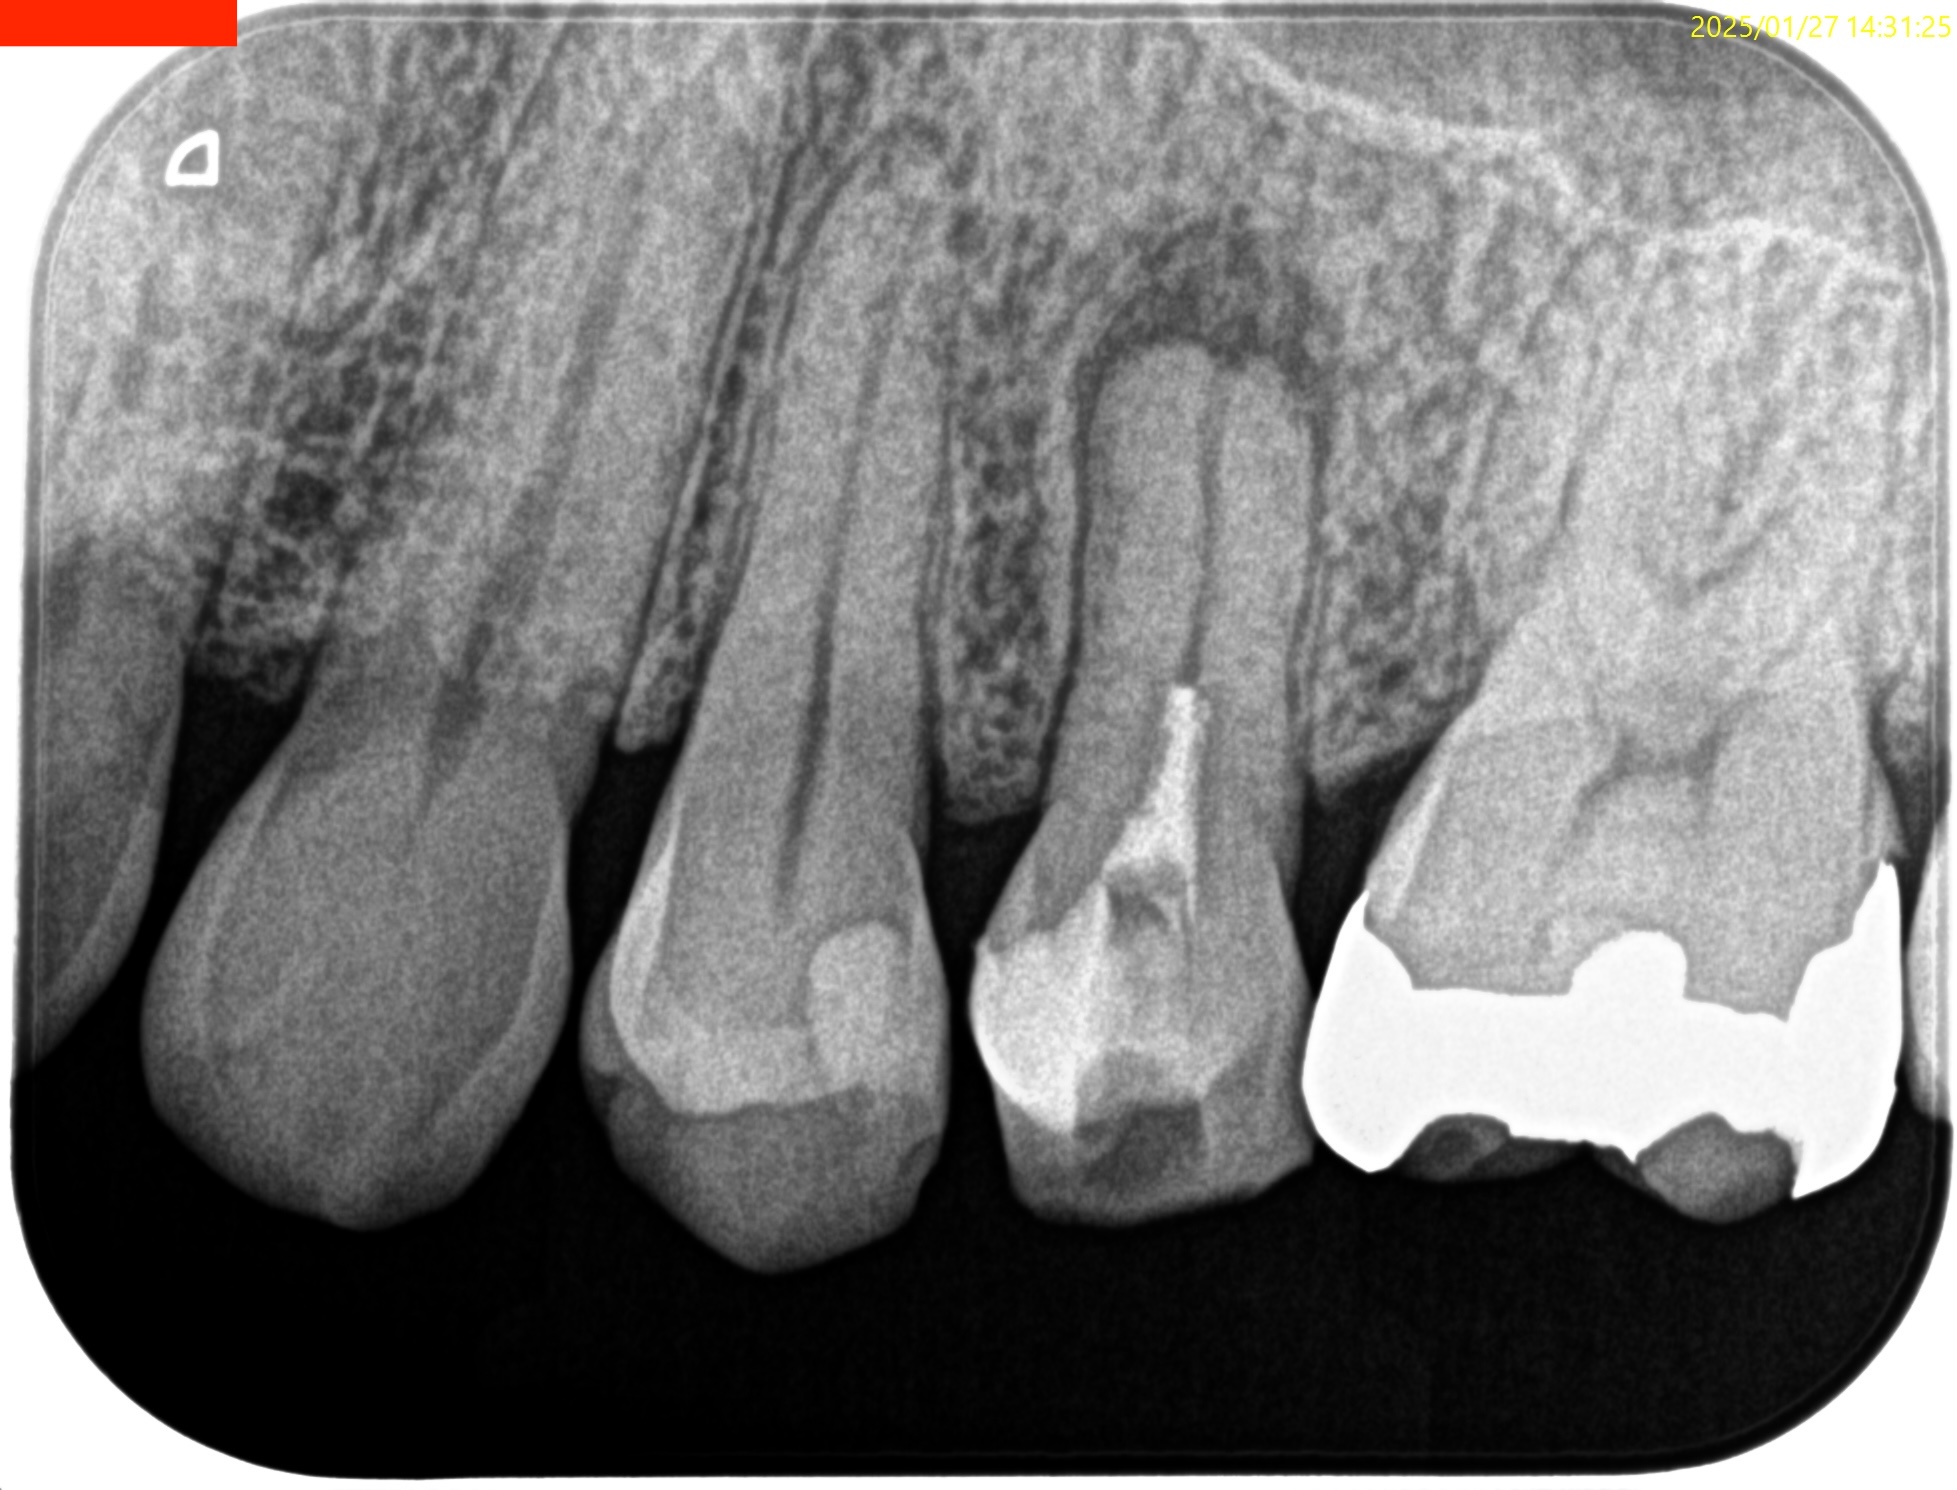

Pre-op Endo Test(2025.1.27)

#13 Cold N/A, Perc.(+), Palp.(+), BT(+), Perio Probe(WNL), Mobility(WNL)

ペリオの問題がない歯だが、PAを撮ると

大きな根尖病変が#13のApex周囲にある。